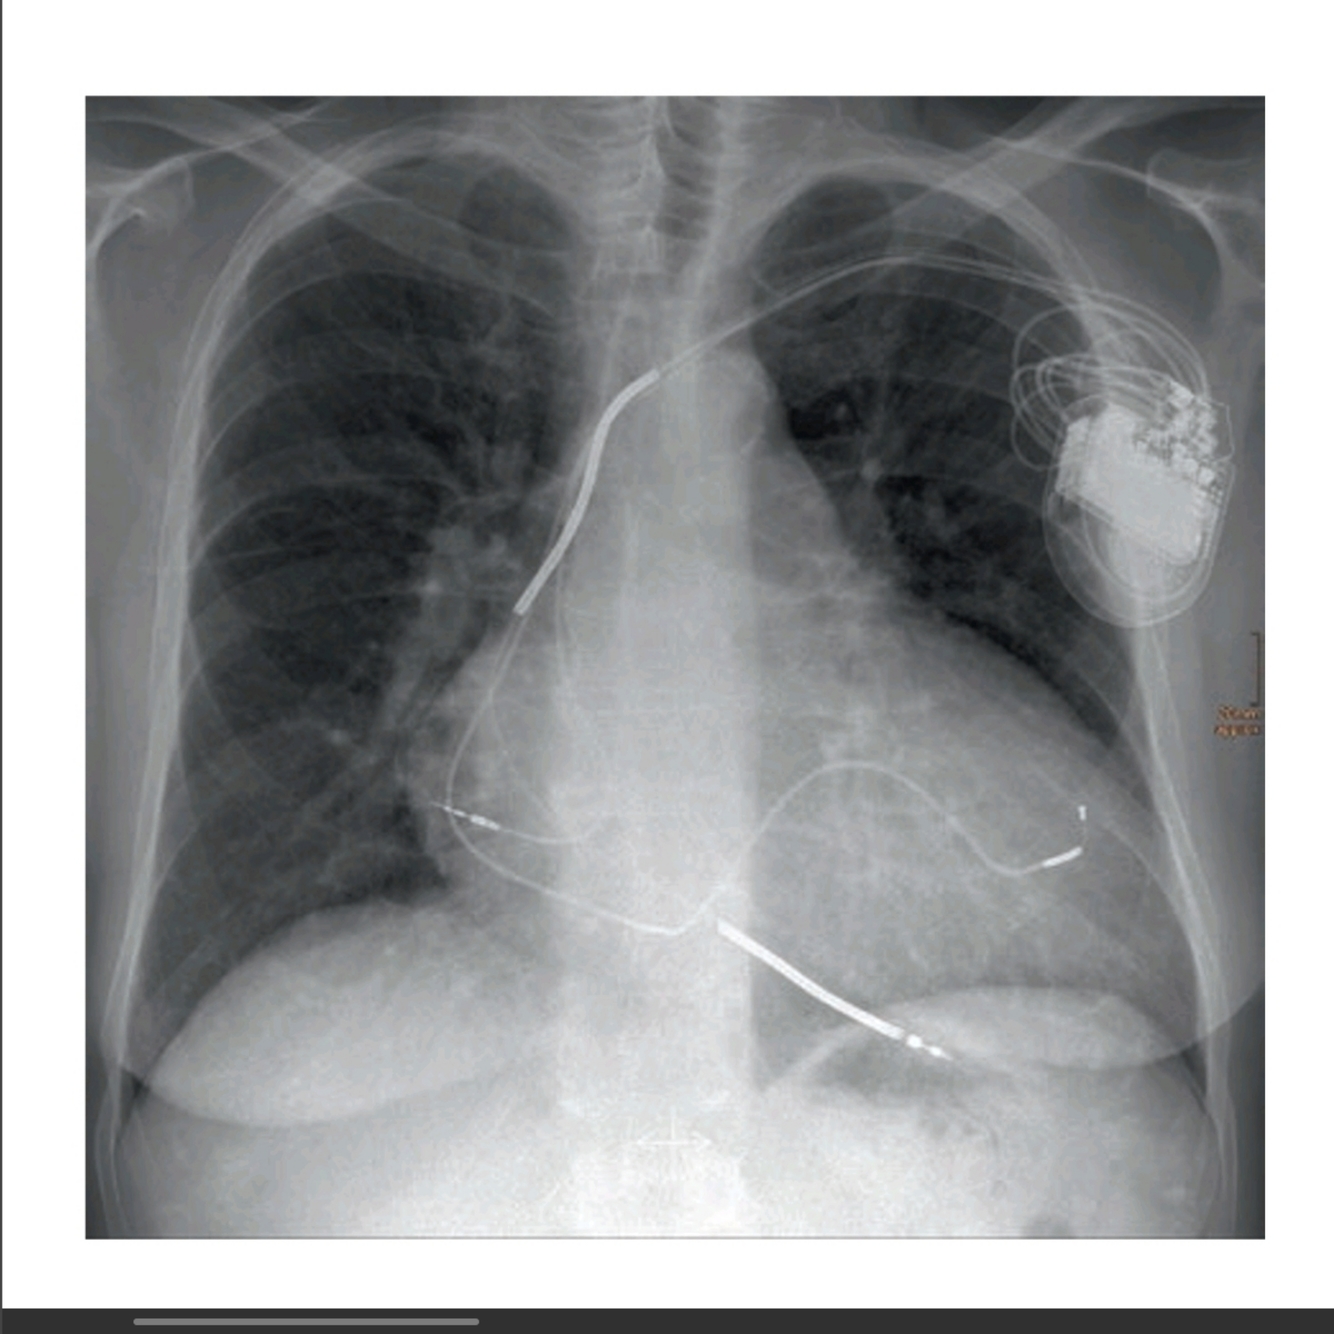

A 65-year-old female after a motor vehicle collision requires emergency surgery for an open lower extremity fracture; the patient tells you she has a “bad heart,” she has no history in your institution, and no signs of heart failure. An EKG shows wide QRS with dual-chamber pacing. A CXR on admission show (See Fig.46.1). 1. What type of device is shown in the image?

This patient has an implantable biventricular cardio-defibrillator (BiV ICD) [1].

(a) The radiographic image of a pacemaker would show (See Fig.46.2):

• Smaller generator

• Discreet right ventricular lead (stable diameter)

• With or without right atrial lead or coronary sinus lead

(b) The radiographic image of an ICD would show above image:

• Larger generator.

• Prominent right ventricular lead, otherwise known as shock coils.

They appear as two metallic segments along the length of the ICD lead.

(c) The radiographic image of a BiV ICD would show (See Fig.46.4):

• Larger generator

• Prominent right ventricular lead (shock coils)

• Right atrium lead

• Coronary sinus lead

Manufacturer ID can be seen in the CXR as well